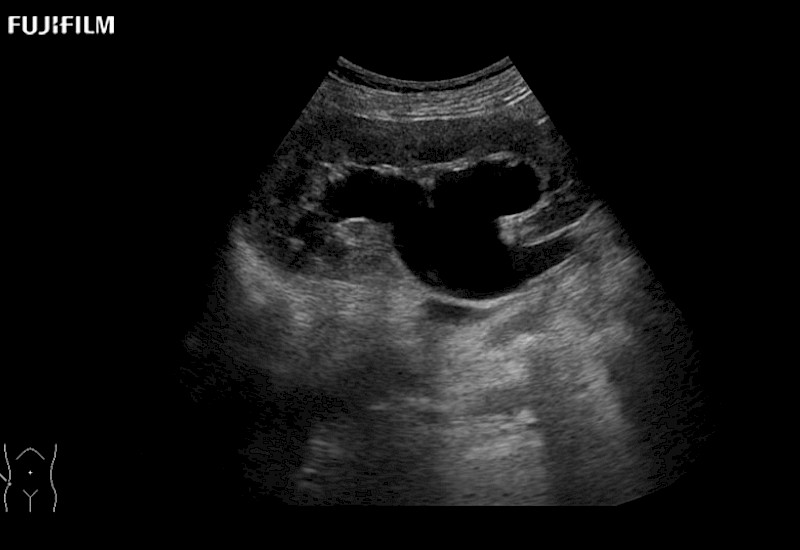

for use during open and laparoscopic procedures: Tumor localization & staging, Ablation, Resection, Biopsy, Transplant, Abdominal exploration, Robotic surgery

Our dedication to Surgical Oncology allows us to offer superior image quality, outstanding system reliability and intuitive use of cutting edge technology.